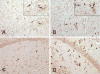

Cerebral malaria complicated by cognitive sequelae is a major cause of morbidity in humans infected with Plasmodium falciparum. To model cognitive function after malaria, we created a rodent model of cerebral malaria by infecting C57BL/6 mice with Plasmodium berghei strain ANKA. After 7 days, an object-recognition test of working memory revealed a significant impairment in the visual memory of infected mice. This impairment was observed in the absence of confounding effects of infection. The cognitive dysfunction correlated with hemorrhage and inflammation. Furthermore, microglial activity and morphological changes detected throughout the brains of infected mice were absent from the brains of control mice, and this correlated with the measured cognitive defects. Similar testing methods in human studies could help identify subjects at risk for an adverse cognitive outcome. This murine model should facilitate the study of adjunctive methods to ameliorate adverse neurological outcomes in cerebral malaria.